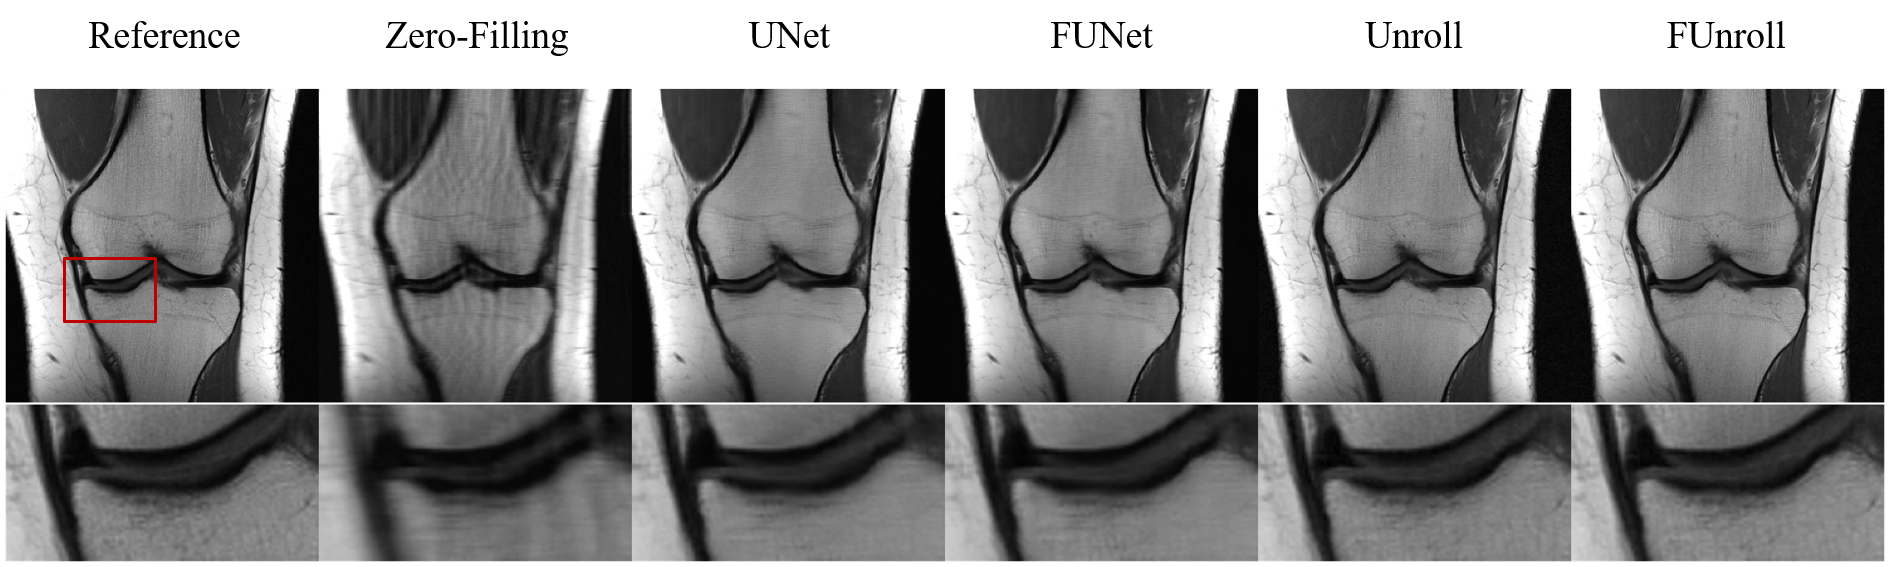

All the quantitative results are shown in Table 1. FCB could improve model’s performance in single-coil and multi-coil data at 4× and 8× acceleration. In particular, the proposed method can get the better numerical results for unroll model in high reduction factor, which indicates that the proposed method have strong robustness. Figure 2 shows the reconstructed result of multi-coil data at 4× acceleration from baseline model and its variant with FCB. The proposed method has the best reconstruction of the meniscus in the unroll model as shown in the red box. Figure 3 shows results at 8× acceleration. It can be seen that the proposed method still has better image reconstruction results under high reduction factor. UNet has a heavy smoothing effect on images and FCB helps to recovery details. For Unroll model, FCB version behaves well in the texture and detail of skeleton and cartilage. Besides, we visualize the trained production kernel in frequency domain as shown in Figure 4. Because Fourier transform is orthogonal, the rank of kernel is constant between frequency domain and spatial domain. The trained kernels have the rank larger than the fixed value of CNN model, which corresponds to large spatial filter with large receptive field.

Figure 3.Example reconstructions of multi coil data at 8 × acceleration. Models with FCB behaves well in the texture and detail of skeleton and cartilage. Models with FCB behave well in the texture and detail of skeleton and cartilage.